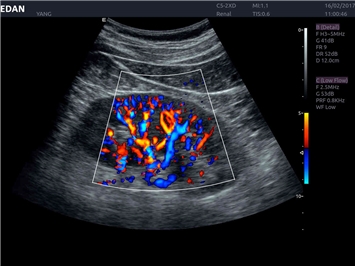

EDAN Acclarix LX4 представляет собой инновационную ультразвуковую систему, построенную на усовершенствованной платформе Acclarix. Сочетание высокого качества визуализации с интеллектуальным рабочим процессом делает эту систему оптимальным выбором для клиник, ценящих эффективность и экономичность.

Передовые технологии визуализации:

Инновационные функции обработки изображений:

• Запатентованная технология адаптивной визуализации тканей

• Функция eSRI для подавления зернистости изображения

• 3D/4D-визуализация с автоматическим редактированием объема (eFace)

• Панорамная визуализация

• Тканевая допплеровская визуализация (TDI)

• Специализированная технология визуализации иглы

Трехмерная реконструкция ЦДК:

Да

Энергетический допплер:

Цветовой допплер: